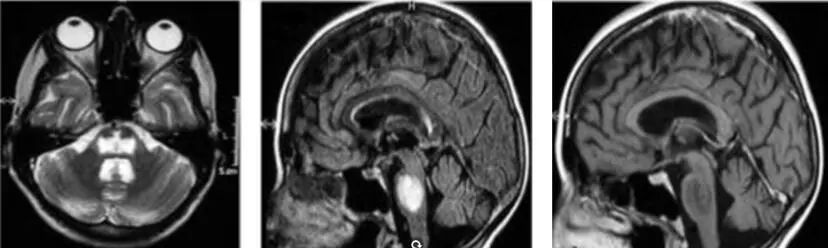

慢性低钠血症患者快速补钠后,逆转细胞内外渗透梯度,引起脑细胞脱水及萎缩,从而引起中央脑桥脱髓鞘症(图1)。临床表现:在原发病基础上,突然出现四肢弛缓性瘫痪,咀嚼、吞咽及言语障碍,眼球震颤,眼球协调运动障碍,缄默,完全或不完全闭锁态势。预后差,死亡率极高,数日-数周内可以导致死亡。治疗:支持、对症治疗为主。甘露醇、速尿、大剂量激素冲击治疗、高压氧、血浆置换治疗。2007年低钠血症指南要求24小时内钠浓度增加小于10-12mmol/L,48小时内增加小于18mmol/L。

图1 渗透性神经系统脱髓鞘疾病脑部病变